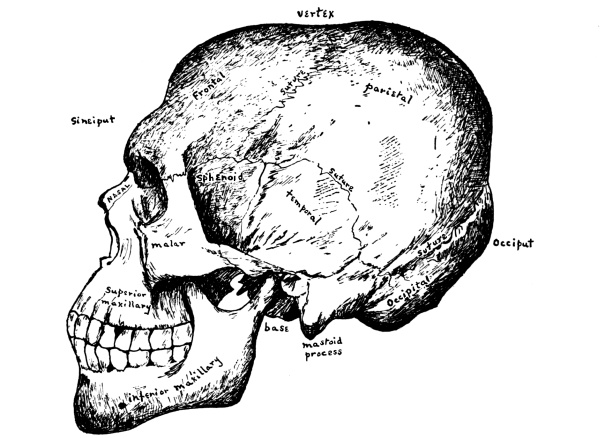

The intelligence and all the special senses, except the sense of touch already spoken of, are gathered together compactly in the head, where they are carefully protected with bony tissue. Covering the brain is the skull or cranium, which is made up of eight bones, the frontal, the occipital, two parietal, two temporal, the sphenoid, and the ethmoid, while the bones of the face are fourteen in number, two nasal, two superior maxillary, two lachrymal, two malar, two palate, two inferior turbinated, the vomer, and the inferior maxillary. For the most part the bones are arranged in pairs, one on either side.

The Cranial Bones.—The cranium or skull is especially adapted for the protection of the brain and the bones are flat and closely fitted to its surface. They have two layers of bone, the outer and the inner tables, of which the outer is the thicker, and between these is a tissue filled with blood-vessels, the diploë. In the infant, whose brain has not yet attained its full size, opportunity must be left for growth and the skull therefore consists of a number of bones with interlocking notched edges, where growth takes place, but in the adult it forms one solid covering of bone.

The line where the edges of two cranial bones come together is called a suture. The suture between the frontal bone and the forward edges of the two parietal bones is called the coronal suture, that between the two parietal bones at the vertex of the skull is known as the longitudinal or sagittal suture, and that between the occipital bone and the back edges of the parietal bones as the lambdoidal suture. [Pg 49]

The frontal bone, as its name implies, forms the fore part of the head or forehead. It joins the parietal bones above and the temporal bones on either side. At the lower edge are the supra-orbital arches, each with a supra-orbital notch or foramen on its inner margin for the passage of the supra-orbital vessels and nerve, the nerve most affected in neuralgia. Just above the arches on either side are the superciliary ridges, behind which, between the two tables of the skull, lie the frontal sinuses. On the inner surface the frontal sulcus for the longitudinal sinus runs along the median line.

The parietal bones are the side bones of the skull. They meet [Pg 50] each other in the sagittal suture at the median line above and join the frontal and occipital bones at either end, while below they touch upon the temporal bones, the temporal muscles being attached in part along their lower surface. These muscles are inserted into the coronoid process of the lower jaw, which they thus help to raise and to retract.

The occipital bone is at the base of the skull and at birth consists of four pieces. In the lower, anterior part is the foramen magnum, an oval opening through which the spinal cord passes from the skull down into the spinal canal. Half way between the foramen and the top of the bone is the external occipital protuberance for the attachment of the ligamentum nuchæ which holds the head erect. The inner side of the bone is deeply concave and is divided by a cross-shaped grooved ridge into four fossæ, the internal occipital [Pg 51] protuberance being situated where the arms of the cross meet. The occipital lobes of the cerebrum lie in the two upper fossæ and the hemispheres of the cerebellum in the two lower ones. In the grooves upon the ridge are the sinuses which collect the blood from the brain.

The temporal bones—said to be so named because the hair over them is the first to turn with age—are situated at the sides and base of the skull and are in three portions: the squamous or scale-like, the mastoid or nipple-like, and the petrous or stony portion. The squamous is the upper portion and has projecting from its lower part the long arched zygomatic process, which articulates with the malar bone of the face and from which arises the masseter muscle, one of the chief muscles of mastication, which has its insertion in the ramus and angle of the lower jaw. Just above the zygomatic process the temporal muscle has its origin in part, while below is the glenoid fossa for articulation with the condyle of the lower jaw, the posterior portion of the fossa being occupied by part of the parotid gland.

Fig. 17.—Side view of the skull.

(After Sobotta.)

The petrous portion, which contains the organ of hearing, is between and somewhat behind the other two portions, at the lower edge of the temporal bone, wedged between the sphenoid and the occipital bones. On its outer surface is the external auditory meatus, and from below projects a long sharp spine called the styloid process, to which several minor muscles are attached. In the same angle between the petrous and squamous portions lies the bony Eustachian tube.

The sphenoid or wedge bone, so called because in the process of development it serves as a wedge, lies at the base of the cranium, forming as it were the anterior part of the floor of the [Pg 53] cavity containing the brain. It is a large, bat-shaped bone and articulates with all the cranial and many of the facial bones, binding them all together. It has a body, two large wings, and two lesser wings and, appears on the outside of the skull between the frontal and the temporal bones behind the zygomatic process. In the adult the body of the sphenoid is hollowed out into the sphenoid sinuses, in which pus sometimes forms.